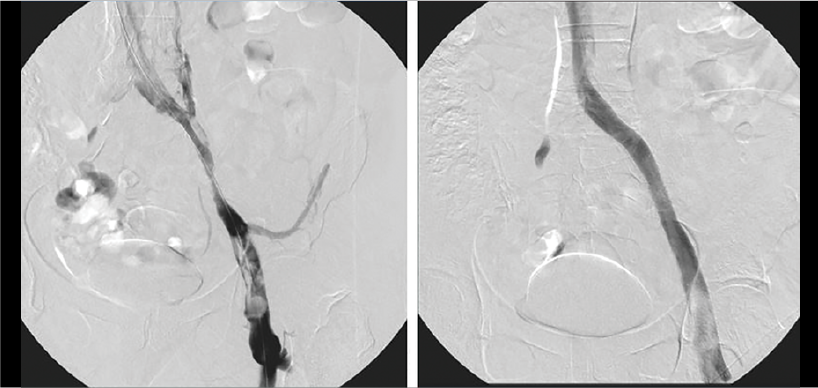

In a perfect world, you are done when you get 100% of the thrombus out, but this is not realistic nor possible. My approach is to get all the fresh, removable thrombus out of the veins. Of course, you may need to stent anyway, because of the underlying reason, like May-Thurner syndrome or other compression areas. The technology of mechanical thrombectomy plus lesion-based stenting, I think, goes hand in hand. You remove the fresh thrombus with Aspirex™ Thrombectomy System and leave in the nonremovable organized material that you then need to stent. With this approach, you first declot the removable thrombus with mechanical thrombectomy and can end the case by stenting only the underlying reason, which is typically May-Thurner syndrome or a compression area.

Treated veins have diameters from 6 to 18 millimeters. The Aspirex™ Thrombectomy System comes in three French sizes: 6, 8, and 10 French. You can use two different techniques in these circumstances. One technique is to use a steerable sheath. It allows me to push the Aspirex™ Catheter against the vessel wall in large veins. The other technique is to use the Toc-toc technique, which was established by Bruno Freitas from Brazil, using the guidewire. If you push on the guidewire a little, it can help push the Aspirex™ Catheter against the vessel wall. This technique definitely requires training, but it works well. Using one of these two techniques allows for the facilitation of thrombus extraction with the Aspirex™ Thrombectomy System by pushing the catheter against the vessel wall, which means the device can also work to remove partially organized wall-adhering material.